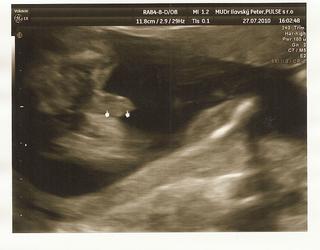

@vladkaz1 uf au mojko.... Ja som dnes vracala 2x zas, nechápem úplna ťažoba a to som jedla diétne kura a ryžu. Ja neviem kedy to už prejde. Ale som rada, že dr mi povedal že malinký je podľa UZV ok.